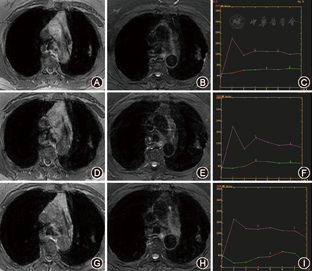

术后1 d消融区最大径为(56±23) mm,而后逐渐缩小。术后1 d~1个月,消融区未见明确强化,时间-信号曲线呈直线型(图1,表2),术后3~12个月,呈轻度延迟强化的"流入型"(图2,表2)。术后3个月,19个(73.1%)呈楔形,7个(26.9%)呈类圆形(图2A,图2B)。

术后1年随访,复发者共4个,均在术后3个月,且术后1周边缘低信号环不完整,复发部位不在进针路径,位于环缺失处。

氩氦刀术后消融区信号改变和病理生理改变密切相关。氩氦刀术后1 d消融区冰球形成并肺组织损伤、出血,本研究术后1 d MRI消融区信号混杂,并周围实变和炎症,提示局部肺组织损伤[14,15]。术后1周消融区发生凝固性坏死[16,17],消融区周围炎症减少,提示周围轻度冻伤肺组织修复[18]。术后1个月,消融区T2WI上信号增高,代表了消融区修复[14],肝脏射频消融的动物实验研究[7,17]也有相同发现。术后1周22个消融区边缘出现完整的低信号环,可能是消融区边缘损伤肺组织肺泡气体潴留所致,也有文献[14,15]认为与冰球内部温度有差别有关。术后1周低信号环完整的22个病灶均未复发,而4个复发病灶环均不完整,位置就发生在环缺口处。因此,术后1周消融区边缘是否存在完整的低信号环有助于判断复发。